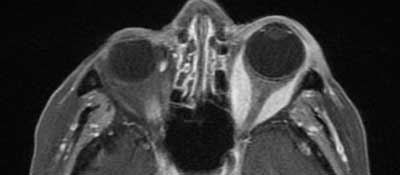

Figure 3

Contrast-enhanced fat suppressed axial T1-weighted MR-images of the orbit confirm fusiform thickening of the left medial and lateral muscles. No extension of intra-orbital changes into the cavernous sinus is seen.